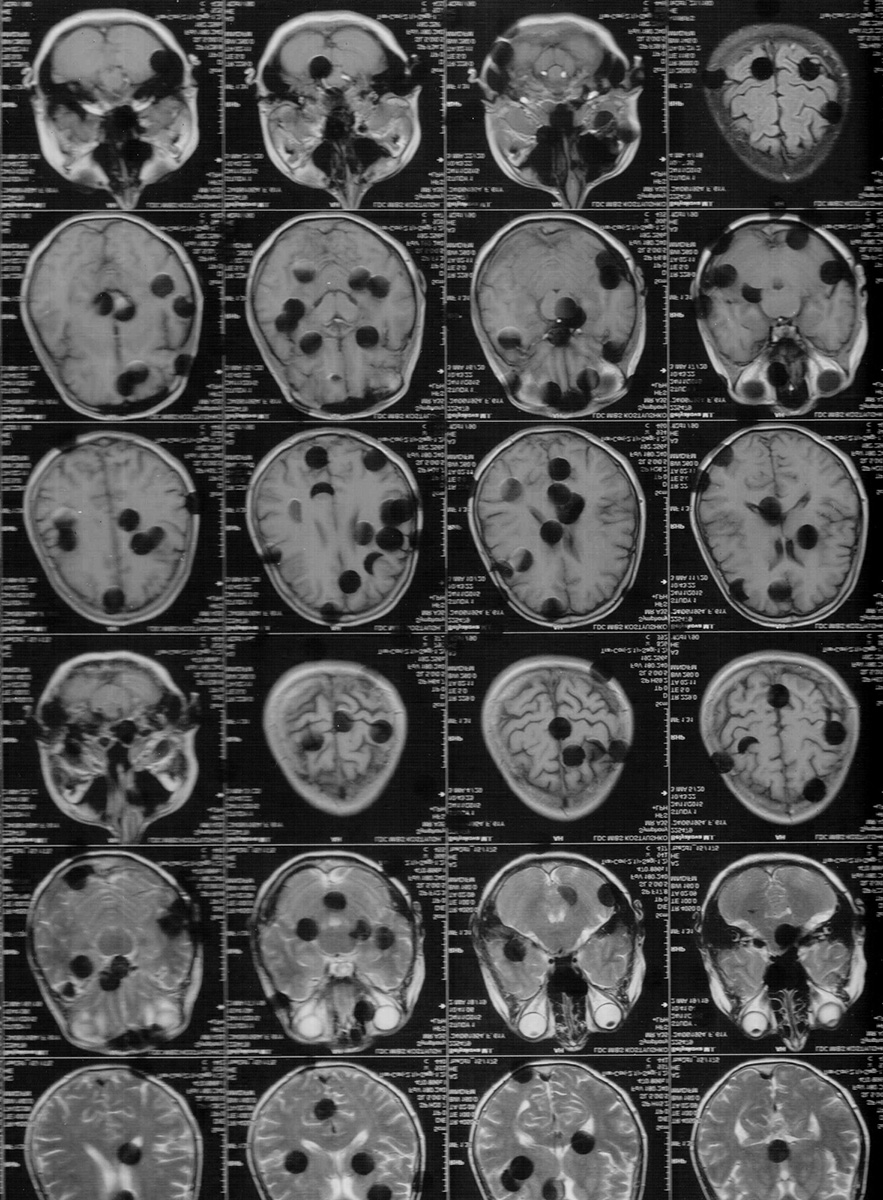

Слева: МРТ головного мозга, испещренного пробелами и дырами. Болезнь Паркинсона разрушает нервные клетки в черной субстанции, отвечающей за движения, оставляя пустоты — как в ткани мозга, так и в повседневной жизни. Справа: руки скрывают лицо. В центре — ожог, тихая метка исчерпанности, точка, за которой начинается пустота

МРТ головного мозга, испещренного пробелами и дырами. Болезнь Паркинсона разрушает нервные клетки в черной субстанции, отвечающей за движения, оставляя пустоты — как в ткани мозга, так и в повседневной жизни